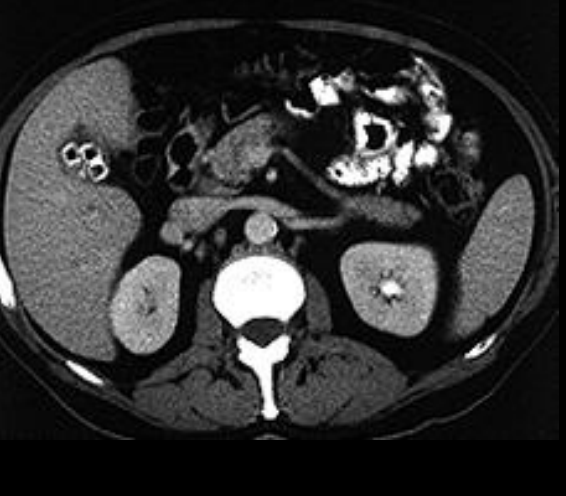

Q

¿Qué hallazgo se puede ver en TC si los litos son cálcicos?

A

Hiperdensidad

(colesterol ⭢ hipodensos)

☮ (centro hipodenso)